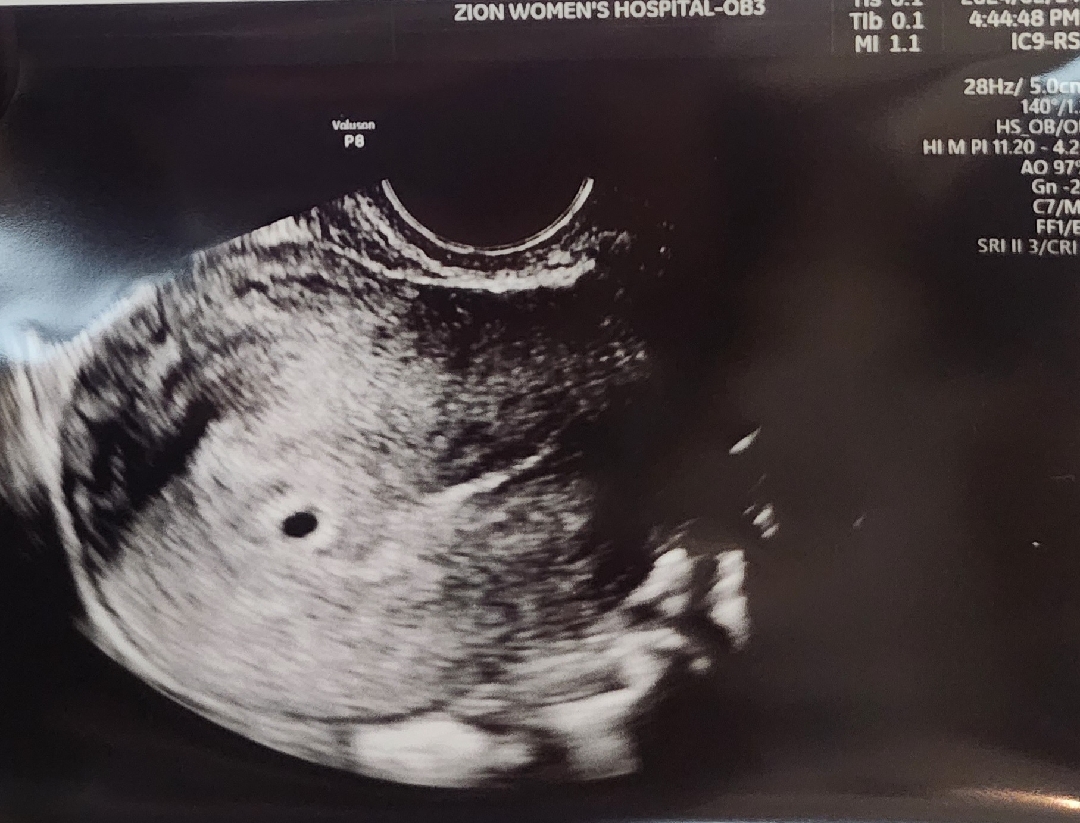

5주차 첫 아기집 보구왔어욤

막생 1/7 이고 , 일주일전 두줄확인뒤 오늘 초음파 보고왔는데 아주 쪼꼼한 아기집이 보였어요!! 아마 몇일 빨리 왔으면 안보였을거라 하시더라구용 ! 얼른 건강하게 커서 봤으면 좋겠네요ㅠㅠ ㅎㅎ

감사합니다 ㅎㅎ 검은콩처럼 생겼어용